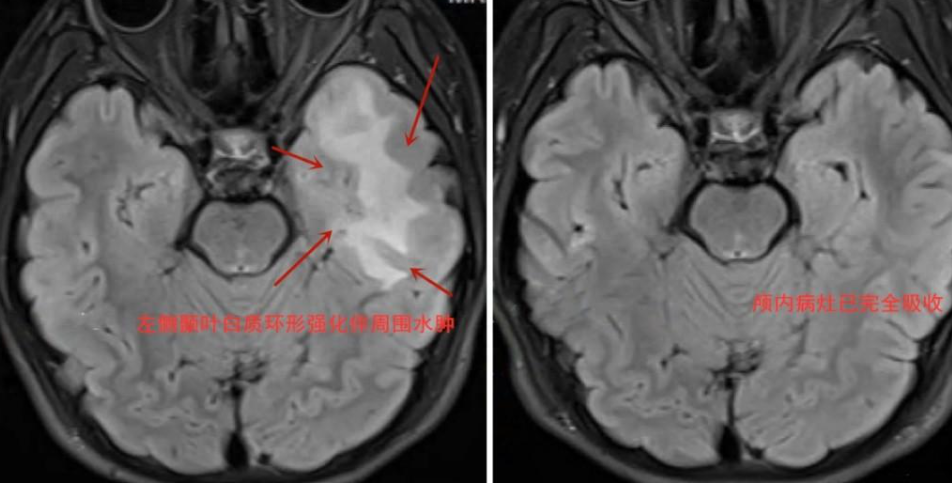

互认外院检验检测结果,医生细致阅片发现俊俊头部MRI增强可见局限于左侧颞叶白质环形强化伴周围水肿,反复追问患病细节,得知其曾长期与猫亲密接触且清洁不到位等细节,凭借丰富的功能神经疾病诊治经验,王焕明高度怀疑,俊俊极有可能是寄生虫感染侵及颅脑,导致脑部异常放电引起癫痫发作。经完善病原学检查,印证了专家的推测,确实为弓形虫感染引发颅内病变。

经1个月对症驱虫治疗,11月19日复查显示,俊俊颅内的病灶已完全吸收,再未发作癫痫,一家人感激不已。